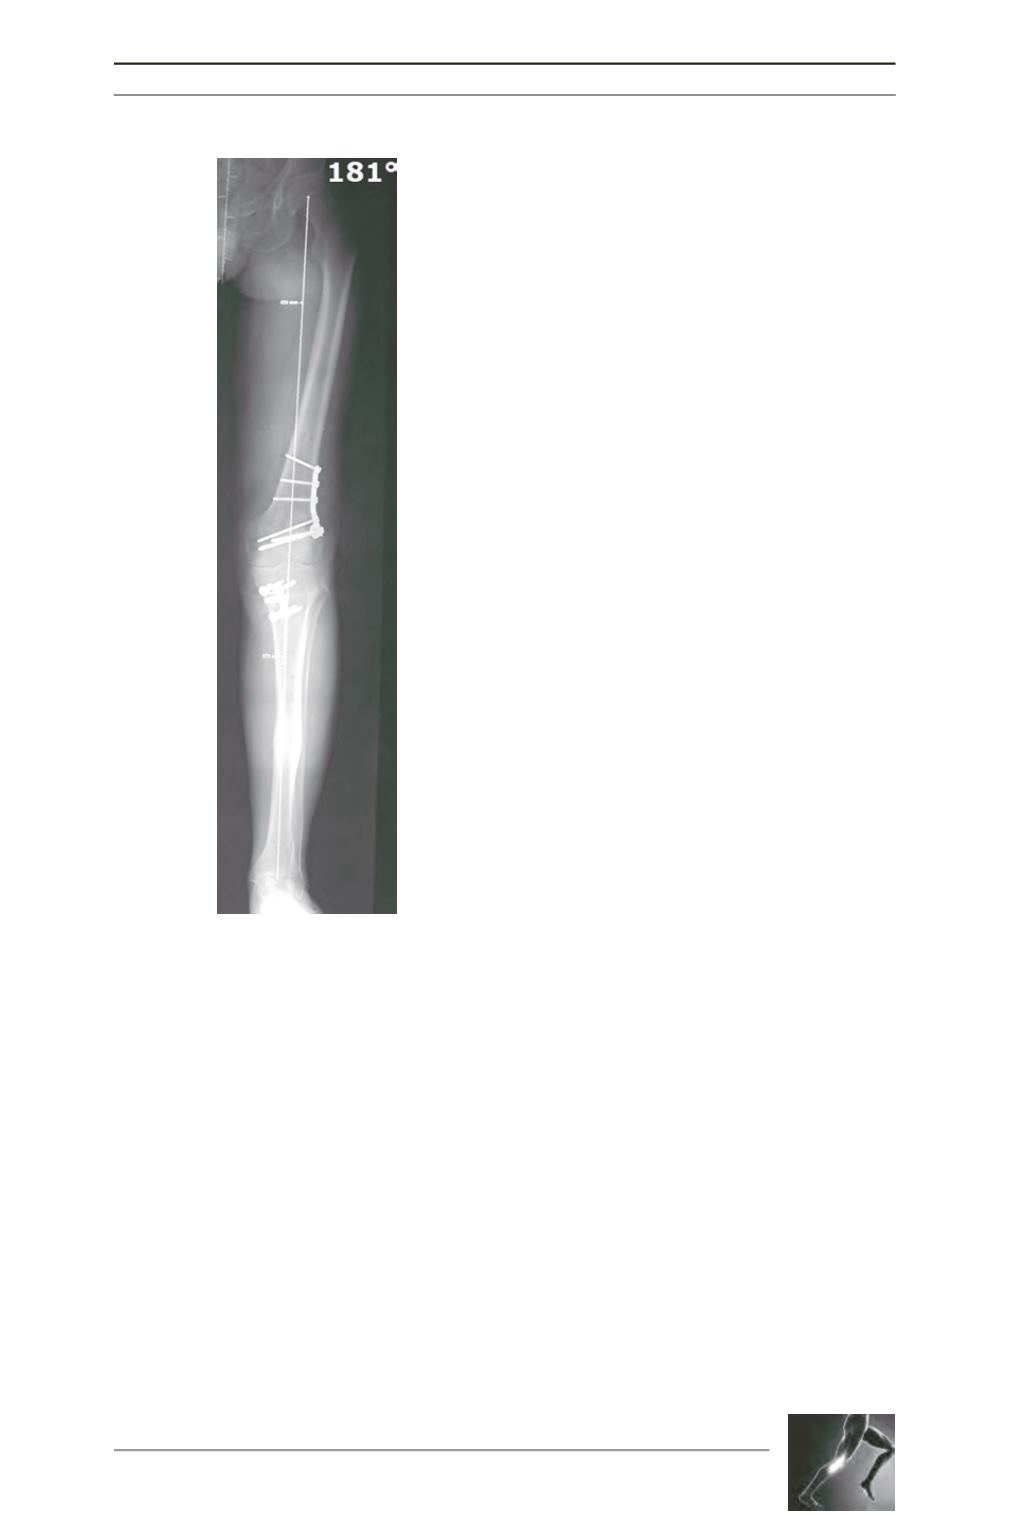

Fig. 4: Standing long leg x-Ray of the

case of figure 2 (6 months follow-up).